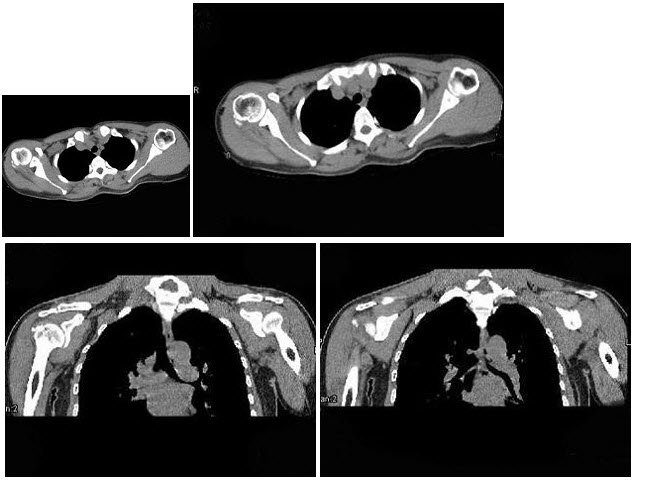

7、单项选择题

男,56岁,尿频、尿急3月余,肉眼血尿1月余,结合所示图像,最可能的诊断()

A.膀胱癌伴出血

B.膀胱结石

C.膀胱憩室伴出血

D.慢性膀胱炎

E.膀胱憩室伴感染

8、单项选择题

根据所提供的图像,最可能的诊断为()

A.出血坏死性胰腺炎

B.脓肿

21、单项选择题

女,64岁,发热、咳嗽1周。胸部CT扫描如下图。

患者抗炎治疗2周后,行胸部CT增强扫描检查,如下图,则最具诊断意义的征象为()

A.多发钙化灶

B.多发含气囊腔

C.多发短毛刺

D.供血动脉起自降主动脉

E.供血动脉起自腹主动脉